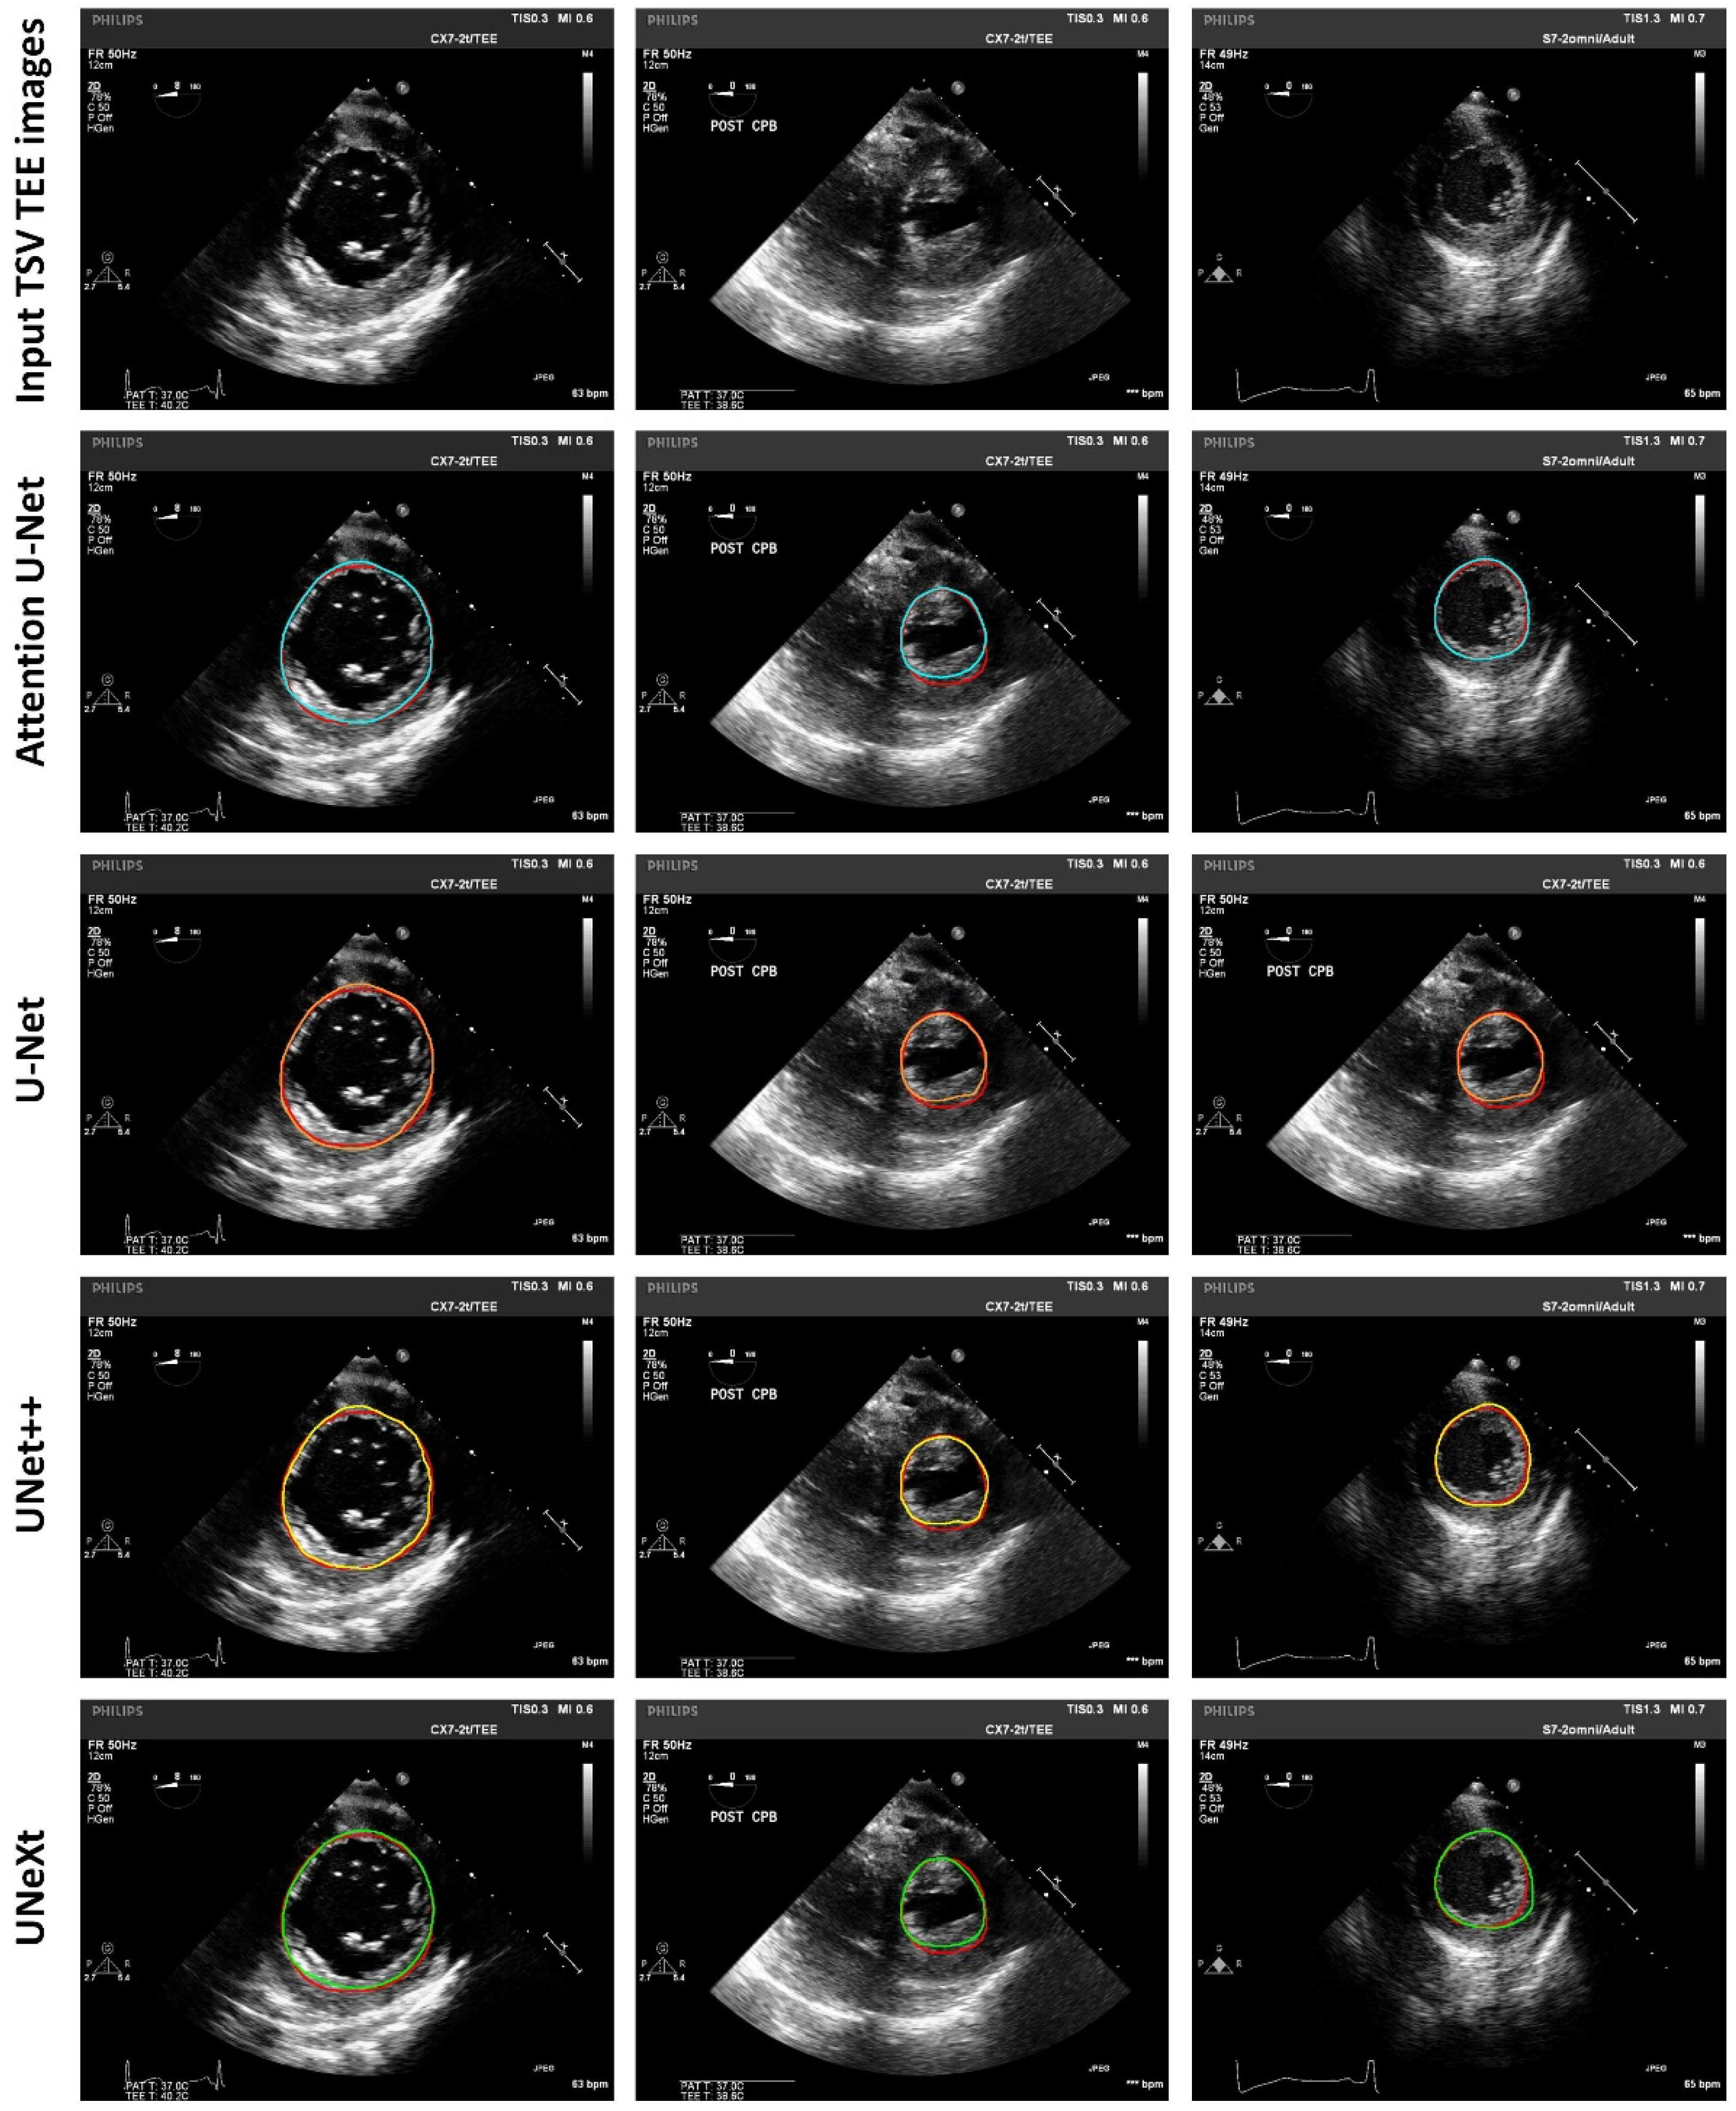

| Deep Learning Models | JSC (%) | DSC (%) |

|---|---|---|

| U-Net [18] | 84.71 ± 10.25 | 90.98 ± 7.19 |

| UNet++ [19] | 86.02 ± 8.70 | 91.76 ± 5.48 |

| UNeXt [20] | 84.20 ± 9.62 | 91.00 ± 6.23 |

| Attention U-Net [21] | 85.93 ± 8.71 | 92.00 ± 5.50 |